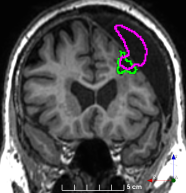

Refer to caption

(a)

(b)

(c)

(d)

(e)

(f)

Figure 3: Manual labels from Rater A (green) and Rater D, the model trained with PubFull + EpiPre + Pseudo (magenta). Errors caused by a (a) small resection, (b) blood clot in cavity and (c) brain shift; segmentations corresponding to the (d) 50th, (e) 75th and (f) 100th percentiles giving a DSC of 81.7, 86.5 and 93.8, respectively.